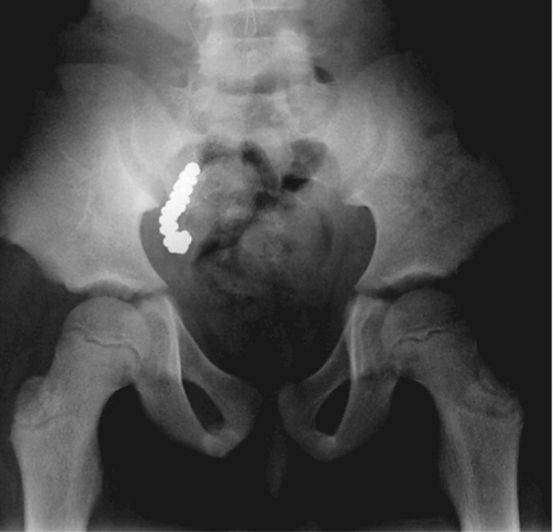

9、吃枪子的阑尾

澳大利亚一名8岁男孩血铅超标(高于正常高线5倍)连续两年,医生一直找不到原因。

一直到患儿发生腹痛,做了个X光检查之后,医生才发现他的阑尾里有57个铅制小球!

之后患儿和其兄弟姐妹告诉医生他们一直在吃家人打猎打来的鹅当中的铅子儿……说白了他们吃了打猎用的*弹铅**。

检查患儿阑尾的医生说这是他行医40年头一次见到的病例,“一生一次”。

这个案例发表在2014年8月的扭英上。